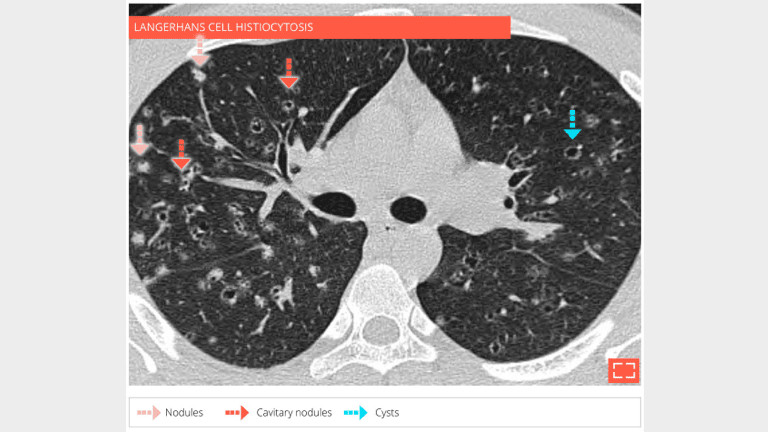

Same patient - coronal reformation shows that the abnormalities are predominating in the upper lungs.